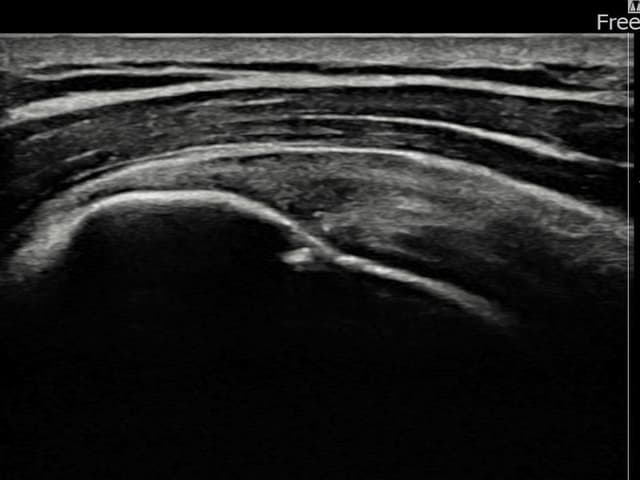

[촬영시기:24.01.08~24.03.14]

[어깨인대 축소봉합술] 좌측 어깨 통증으로 팔을 올리기 불편하여 내원하셨습니다.